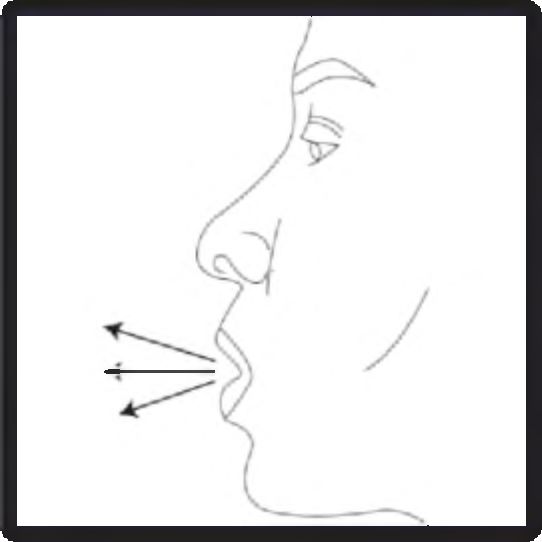

- Hızlı, duraksamadan ve alabildiğiniz kadar derin bir nefes alınız.

6. Nefesinizi olabildiğince dışarı veriniz.